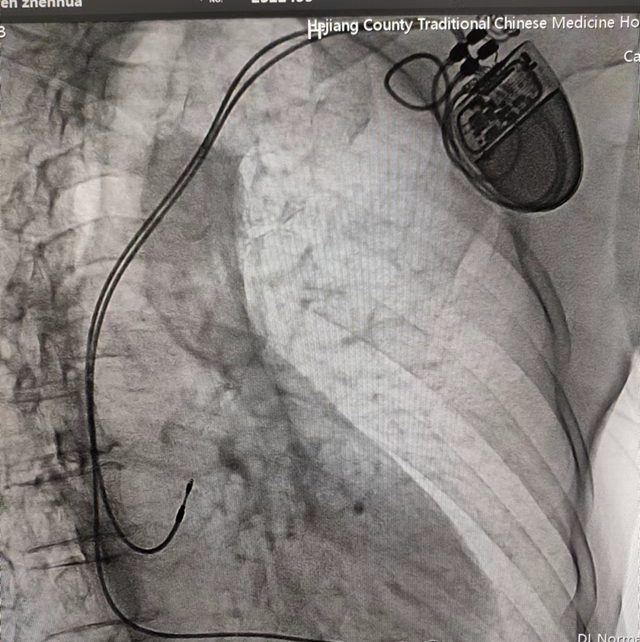

近日,合江县中医医院心血管内科成功为3位高龄心动过缓患者植入人工永久双腔起搏器,实现了医院心脏永久双腔起搏器安置术零突破,为患者心脏装上“保险”!

经过充分的术前准备,由心血管内科主任黄胜主刀,在介入医学中心医护团队默契配合下,成功为患者行永久性心脏起搏器植入术。手术历经1小时左右顺利完成,起搏器感知、起搏功能良好,患者生命体征平稳。近日,科室又为两名患者成功开展了此手术。

人工心脏起搏是用脉冲发生器发放人工脉冲电流刺激心脏,使心脏产生有效收缩的方法,它是治疗缓慢性心律失常和快速心律失常的有效措施。

黄胜介绍,心脏起搏器植入术具有切口小、不开胸、安全系数较高等优势。通过植入心脏起搏器发出的规律脉冲,可以维持心脏的正常跳动和射血功能,最大限度挽救患者生命,大大改善心脏疾病患者的生活质量。